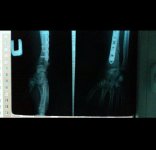

4) Гидравлическое сцепление. После легкой "модернизации" левой руки титановыми запчастями

и легким дискомфортом кисти - как я по нему страдал :dash1:

4) Гидравлическое сцепление. После легкой "модернизации" левой руки титановыми запчастями

и легким дискомфортом кисти - как я по нему страдал :dash1: